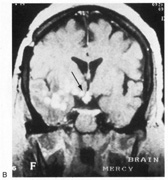

Achromatopsia is caused by lesions of the lingual and fusiform gyri,245,261 as confirmed by modern imaging.240,241,251,254,258,262 Lesions of the middle third of the lingual gyrus or white matter behind the posterior tip of the lateral ventricle may be critical.240,263 Bilateral lesions are necessary for complete achromatopsia.

Achromatopsia is most often caused by strokes. Bilateral sequential or simultaneous infarctions in the territories of both posterior cerebral arteries can occur, or multiple infarcts may result from a coagulopathy.279 Achromatopsia may be the first symptom of a stroke or the outcome of an initial cortical blindness. Other bilateral lesions causing achromatopsia include herpes simplex encephalitis,251 cerebral metastases,258 repeated focal seizures,280 focal dementia,281 and even migraine aura, causing a transient achromatopsia.282 Temporo-occipital white matter damage has caused a reversible dyschromatopsia in one patient with carbon monoxide poisoning,283 a condition that usually causes an apperceptive agnosia with spared color perception.245

HEMIACHROMATOPSIA.

Achromatopsia in the contralateral hemifield alone can follow unilateral right or left occipital lesions (Fig. 18). Patients are typically asymptomatic until the defect is demonstrated on examination.234,235 Hemiachromatopsia is usually associated with a superior quadrantanopia;234,235,241 therefore, the color defect is only demonstrable in the remaining inferior quadrant. The preserved color vision in the ipsilateral hemifield allows normal or near-normal performance on centrally viewed tests of color vision such as pseudoisochromatic plates. The incidence of hemiachromatopsia is probably underestimated, given its asymptomatic nature and the failure of routine clinical color tests to detect its presence.

Fig. 18. Magnetic resonance imaging scan of patient with stroke causing a right hemiachromatopsia as well as partial superior quadrantanopia.